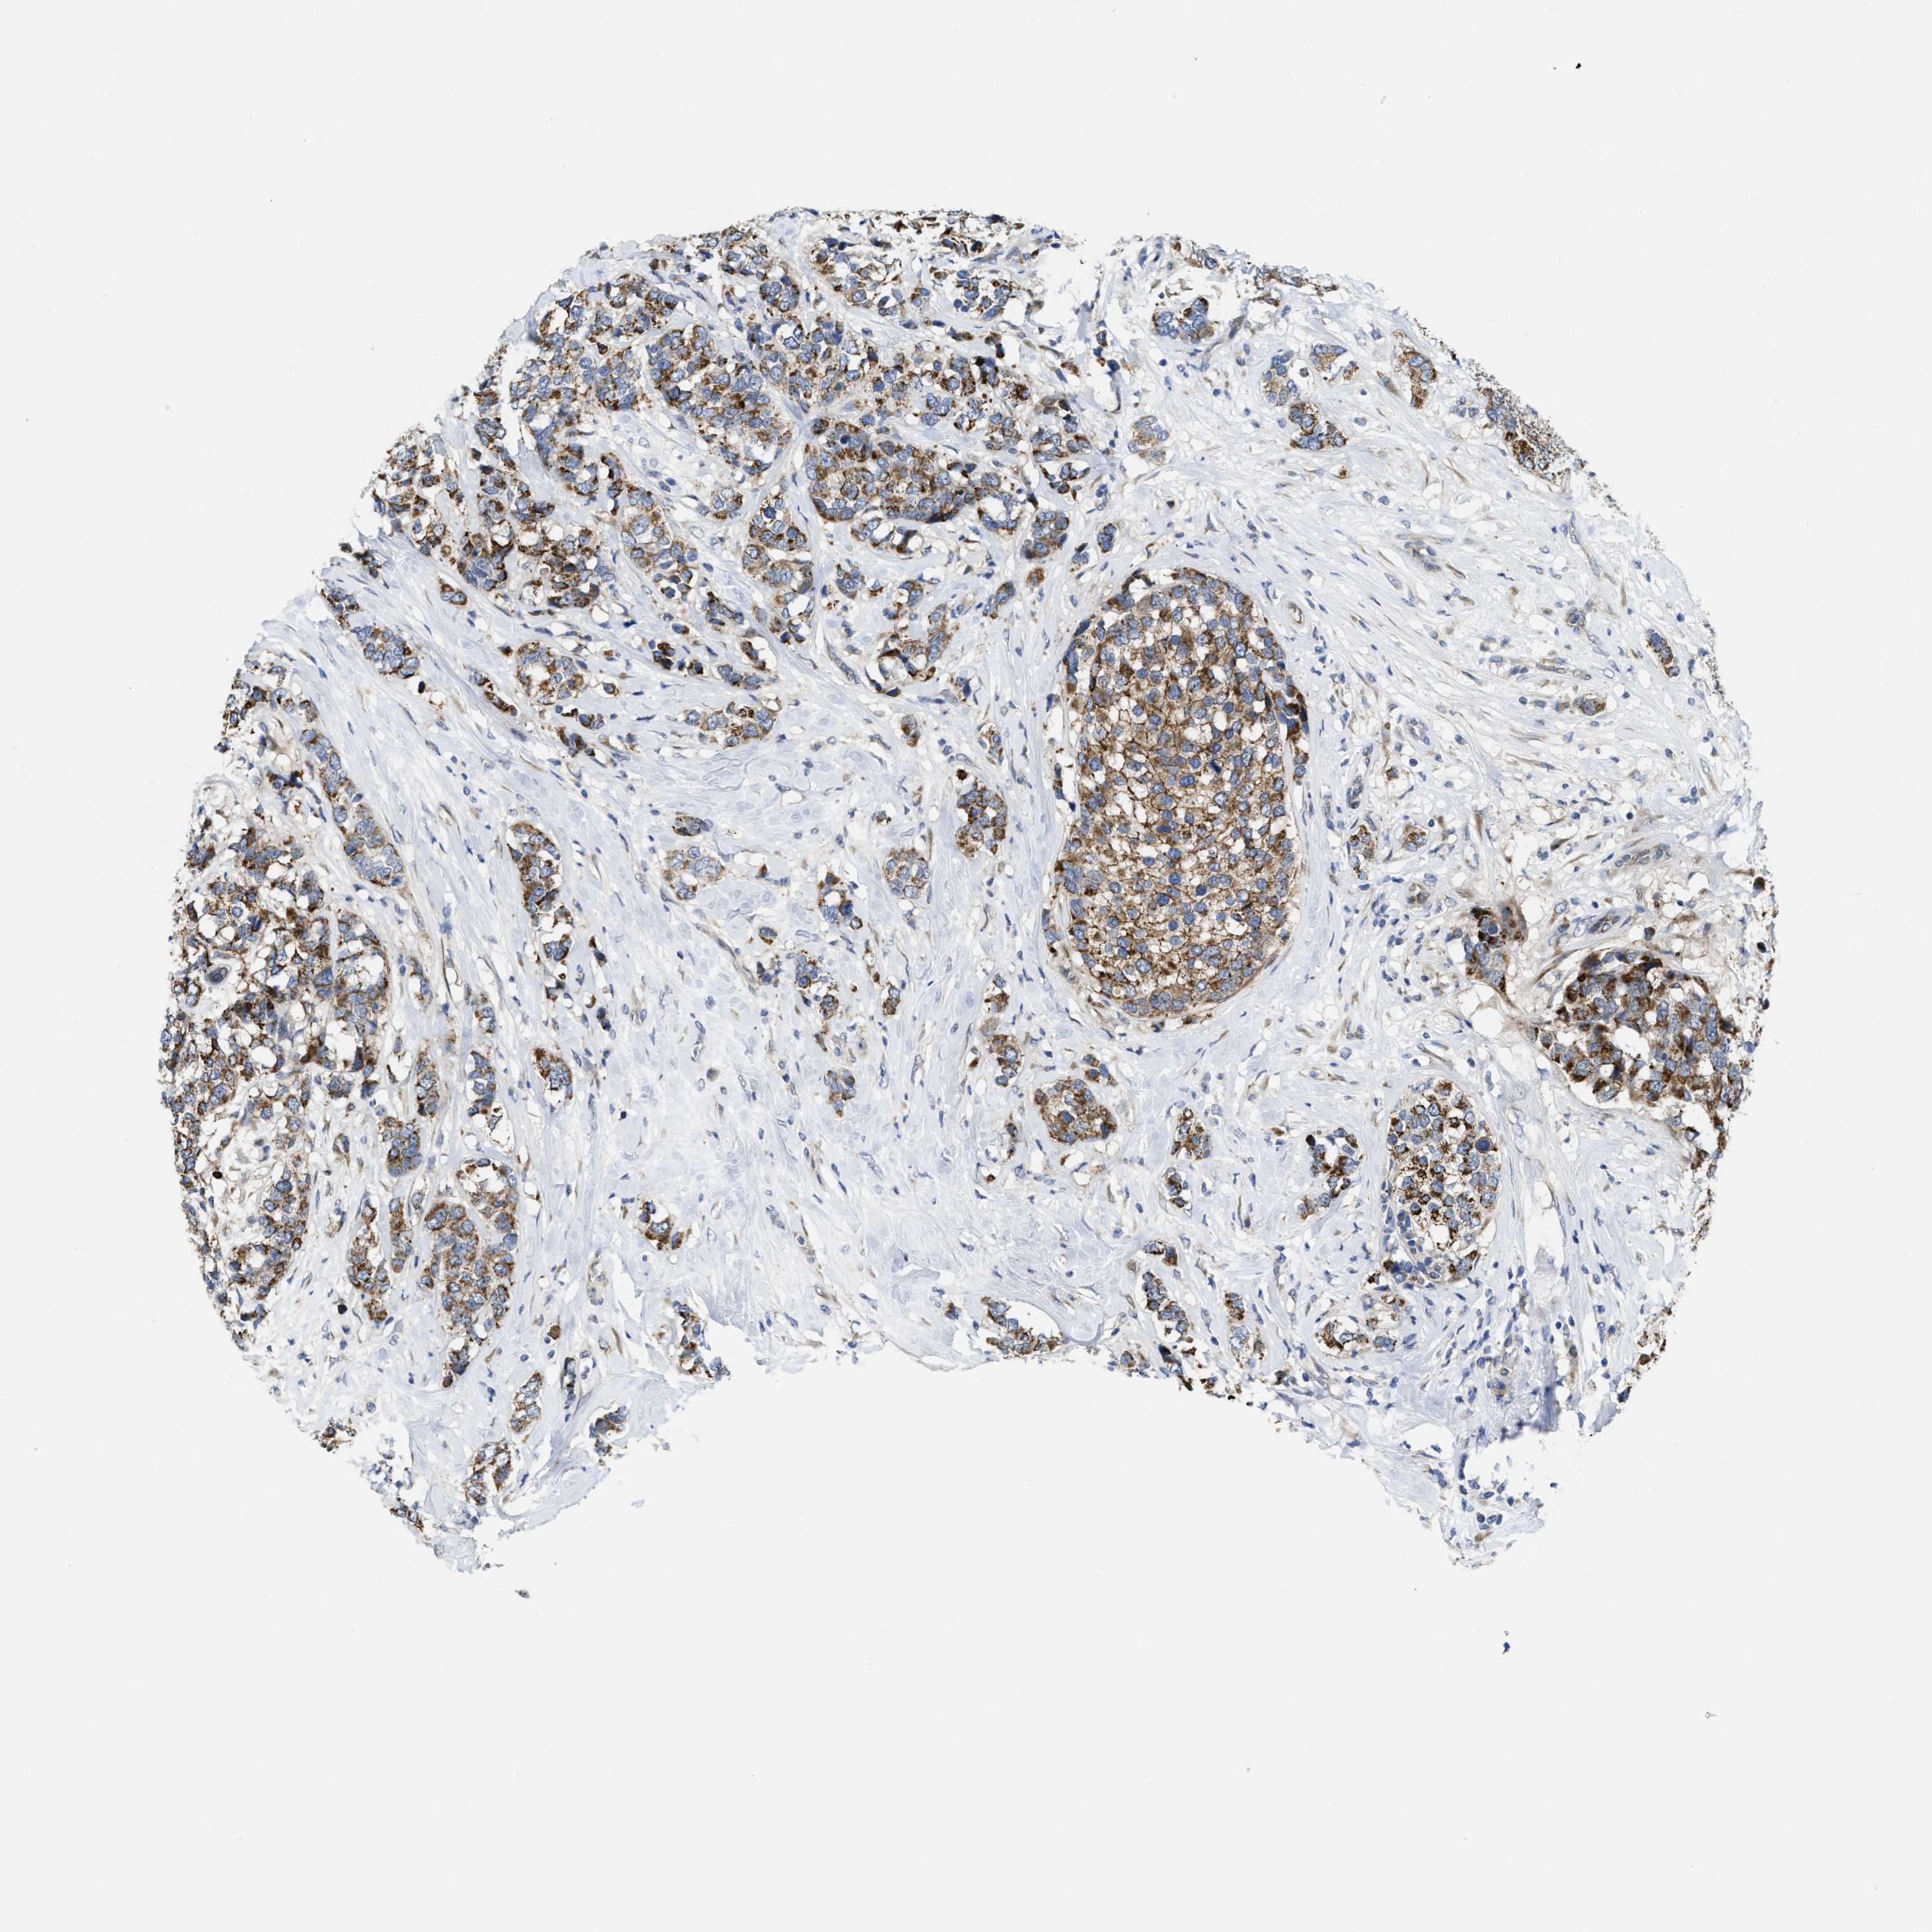

CANCER BREAST CANCER Show tissue menu

BRCA TCGA BRCA VALIDATION PROTEIN EXPRESSION